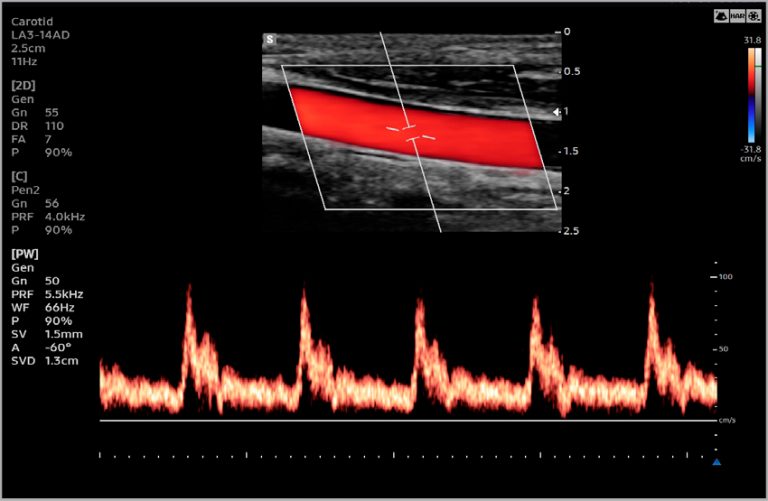

Imagens Clínicas